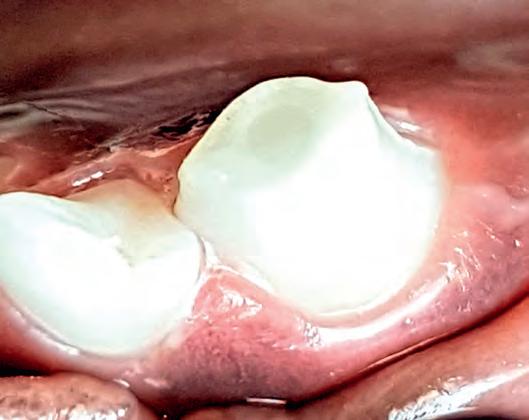

A) Ongecompliceerde fractuur: snel handelen Allereerst is het bij een tandfractuur belangrijk om te weten of het om een oppervlakkige breuk gaat, waarbij alleen een stuk glazuur en een deel van het tandbeen (dentine) afgebroken is. Bij een oppervlakkige breuk is het wortelkanaal nog gesloten: dit noemen we daarom een ongecompliceerde fractuur genoemd.

de inhoud. Het sealen van het bloot liggend tandbeen voorkomt een infectie in het wortelkanaal, mits op tijd uitgevoerd. Bedenk ook dat bij een jonge hond de laag tandbeen erg dun is (zie afbeelding 2) en dat bij een ongecompliceerde fractuur het wortelkanaal in de regel vlak onder een dunne laag tandbeen ligt. Het wortelkanaal kan dus snel geïnfecteerd raken en dus moet er, vooral bij jonge honden, snel behandeld worden!

Een ongecompliceerde fractuur: het wortelkanaal ligt nog onder een (dunne) laag tandbeen.

De behandeling van een ongecompliceerde fractuur bestaat uit het afdichten (sealen) van het tandbeen. Tandbeen is namelijk poreus van structuur: er lopen talloze microscopisch kleine kanalen in het tandbeen waardoor bacteriën zich richting het wortelkanaal kunnen verplaatsen. Er is dus een serieus risico op infectie van het wortelkanaal met uiteindelijk het afsterven van